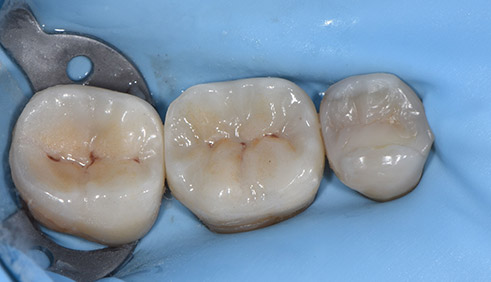

Op de foto's is de voor situiatie en na situatie van de rechter onderkant te zien.

Het kleine kiesje is opgebouwd met composiet en de twee grote kiezen met keramiek (Emax Press).

voor